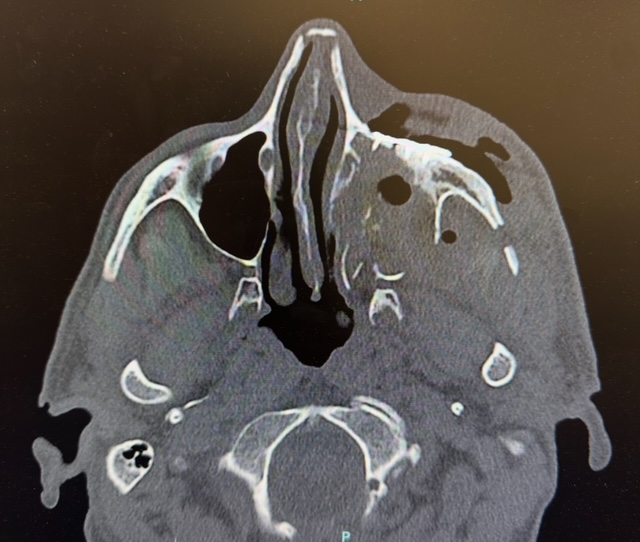

A young male patient presented to Hackensack University Medical Center after sustaining facial injuries subsequent to physical assault. As part of our NJ/NY hospital affiliations, Dr. Feuerstein and team were called to evaluate and treat the case. Imaging confirmed a left Zygomaticomaxillary Complex (ZMC) fracture and a left orbital floor fracture. These injuries affected midface projection, cheekbone position, and the structural support beneath the left eye. Without surgical repair, the patient risked:

The Left ZMC fracture required meticulous repositioning of displaced bone segments. Using multiple surgical approaches to access the facial skeleton, the custom plates designed in the planning phase, secured the cheekbone into its correct anatomical location.

How Was the Orbital Floor Rebuilt?

To restore proper support beneath the eye, the team placed a custom orbital floor implant. This prevented long-term complications such as:

Custom implants allow for a near-exact recreation of the patient’s natural orbital anatomy.